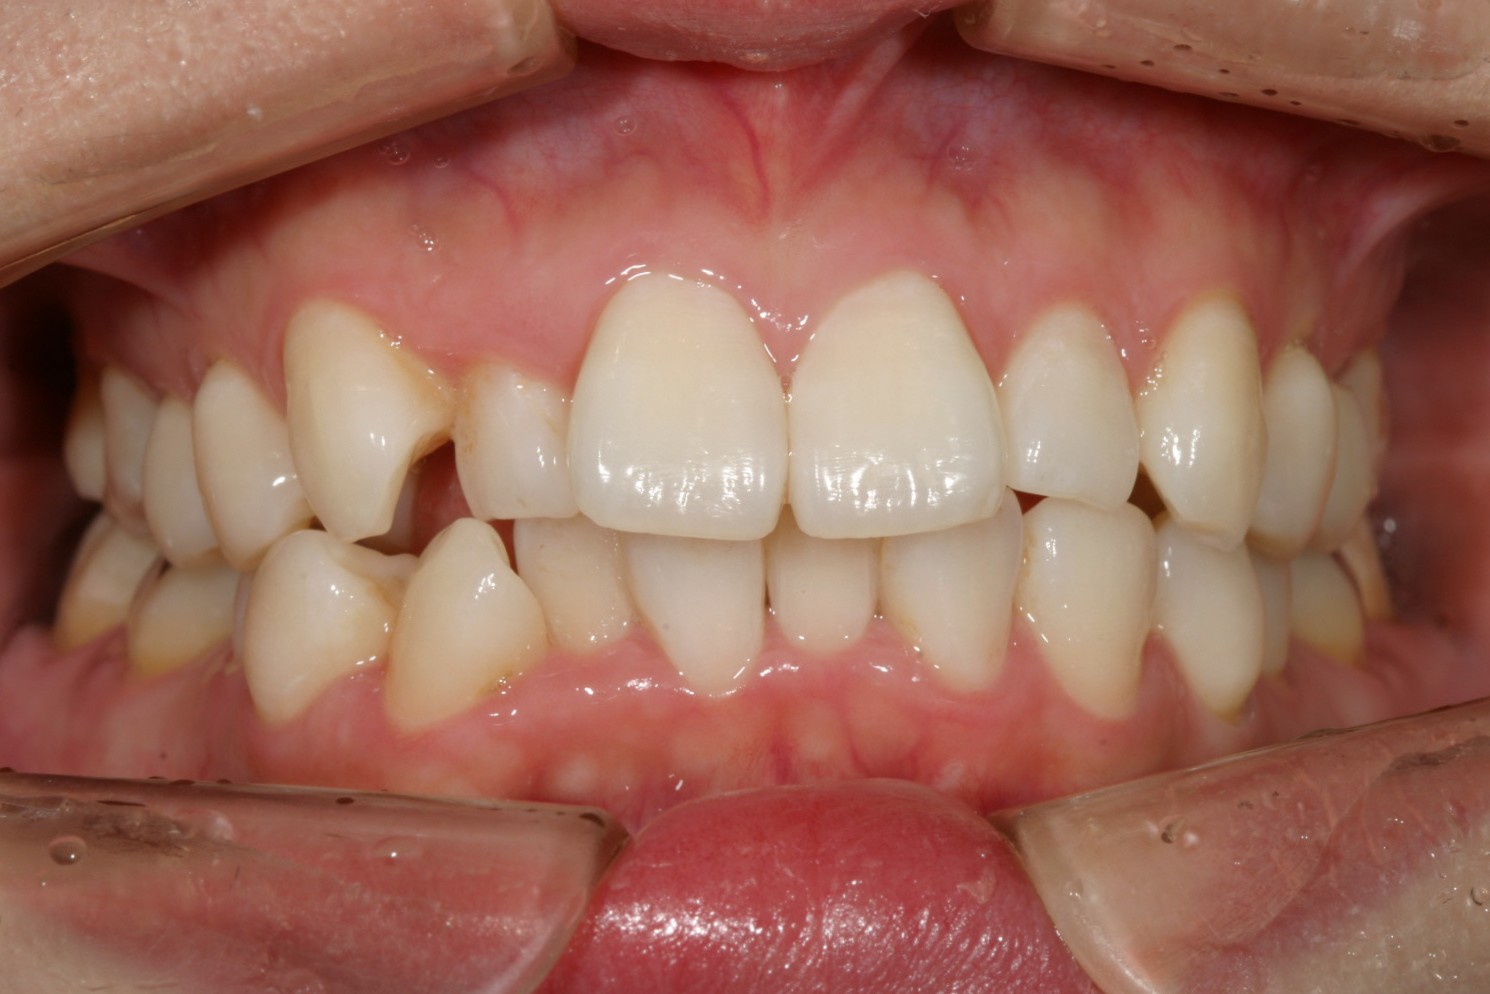

右上の犬歯が飛び出て審美的にも悪く、又ガタガタも気になる。

右側の犬歯の飛び出しが少し気になりますね~

下顎前歯は犬歯間幅径が狭い為ヘビーなガタガタです。

上下顎のオーバージェットが気になります。